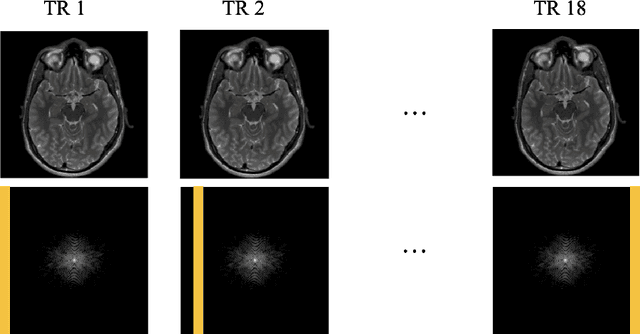

Abstract:Magnetic Resonance Imaging (MRI) is a widely used medical imaging modality boasting great soft tissue contrast without ionizing radiation, but unfortunately suffers from long acquisition times. Long scan times can lead to motion artifacts, for example due to bulk patient motion such as head movement and periodic motion produced by the heart or lungs. Motion artifacts can degrade image quality and in some cases render the scans nondiagnostic. To combat this problem, prospective and retrospective motion correction techniques have been introduced. More recently, data driven methods using deep neural networks have been proposed. As a large number of publicly available MRI datasets are based on Fast Spin Echo (FSE) sequences, methods that use them for training should incorporate the correct FSE acquisition dynamics. Unfortunately, when simulating training data, many approaches fail to generate accurate motion-corrupt images by neglecting the effects of the temporal ordering of the k-space lines as well as neglecting the signal decay throughout the FSE echo train. In this work, we highlight this consequence and demonstrate a training method which correctly simulates the data acquisition process of FSE sequences with higher fidelity by including sample ordering and signal decay dynamics. Through numerical experiments, we show that accounting for the FSE acquisition leads to better motion correction performance during inference.